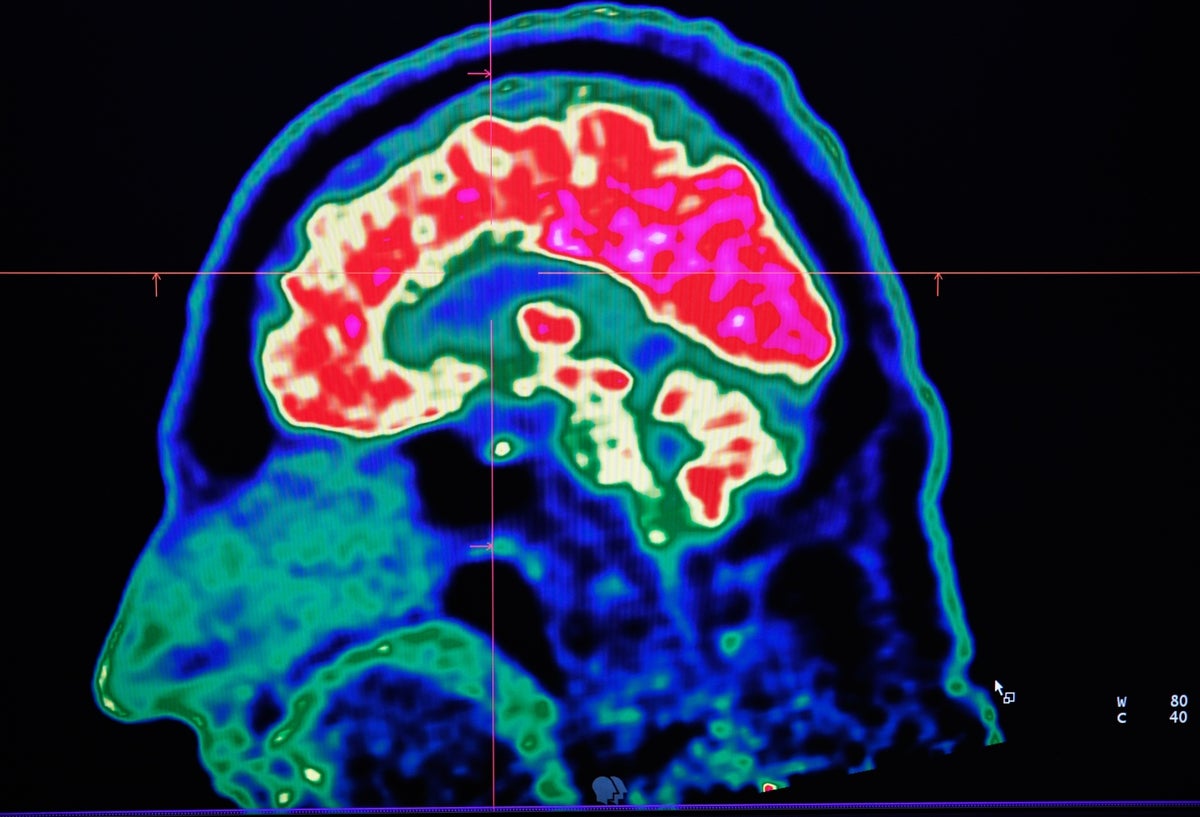

Un grupo de investigadores trabaja en un descodificador que convertirá las señales cerebrales en palabras y permitiría hablar a las víctimas de un accidente cardiovascular o una parálisis, según un estudio publicado el miércoles.

Estos científicos inventaron un descodificador para reproducir palabras sintéticas por computadora, a partir de las señales cerebrales que activan los movimientos correspondientes en la boca.

"Nuestro objetivo a largo plazo es crear una técnica para restablecer la comunicación en pacientes que no pueden hablar, ya sea por problemas neurológicos como accidentes cerebrovasculares o enfermedades como ciertos tipos de cáncer", dijo a la AFP uno de los autores del estudio, Edward Chang, de la Universidad California (UCSF), en San Francisco.

De ahí la idea de los científicos de ir a buscar directamente las palabras a su fuente, el cerebro.

Llevaron a cabo un experimento con cinco pacientes tratados por epilepsia a los que colocaron electrodos en los cerebros.

Los investigadores primero pidieron a estos pacientes que leyeran en voz alta algunas oraciones predefinidas. El objetivo: identificar, gracias a los electrodos, las señales cerebrales responsables de la articulación de las palabras.

Luego, descodificaron estas señales asociando los movimientos necesarios para la pronunciación, en las mandíbulas, la lengua, los labios o la laringe. Finalmente, sobre la base de estos movimientos, reprodujeron dichas oraciones por computadora.